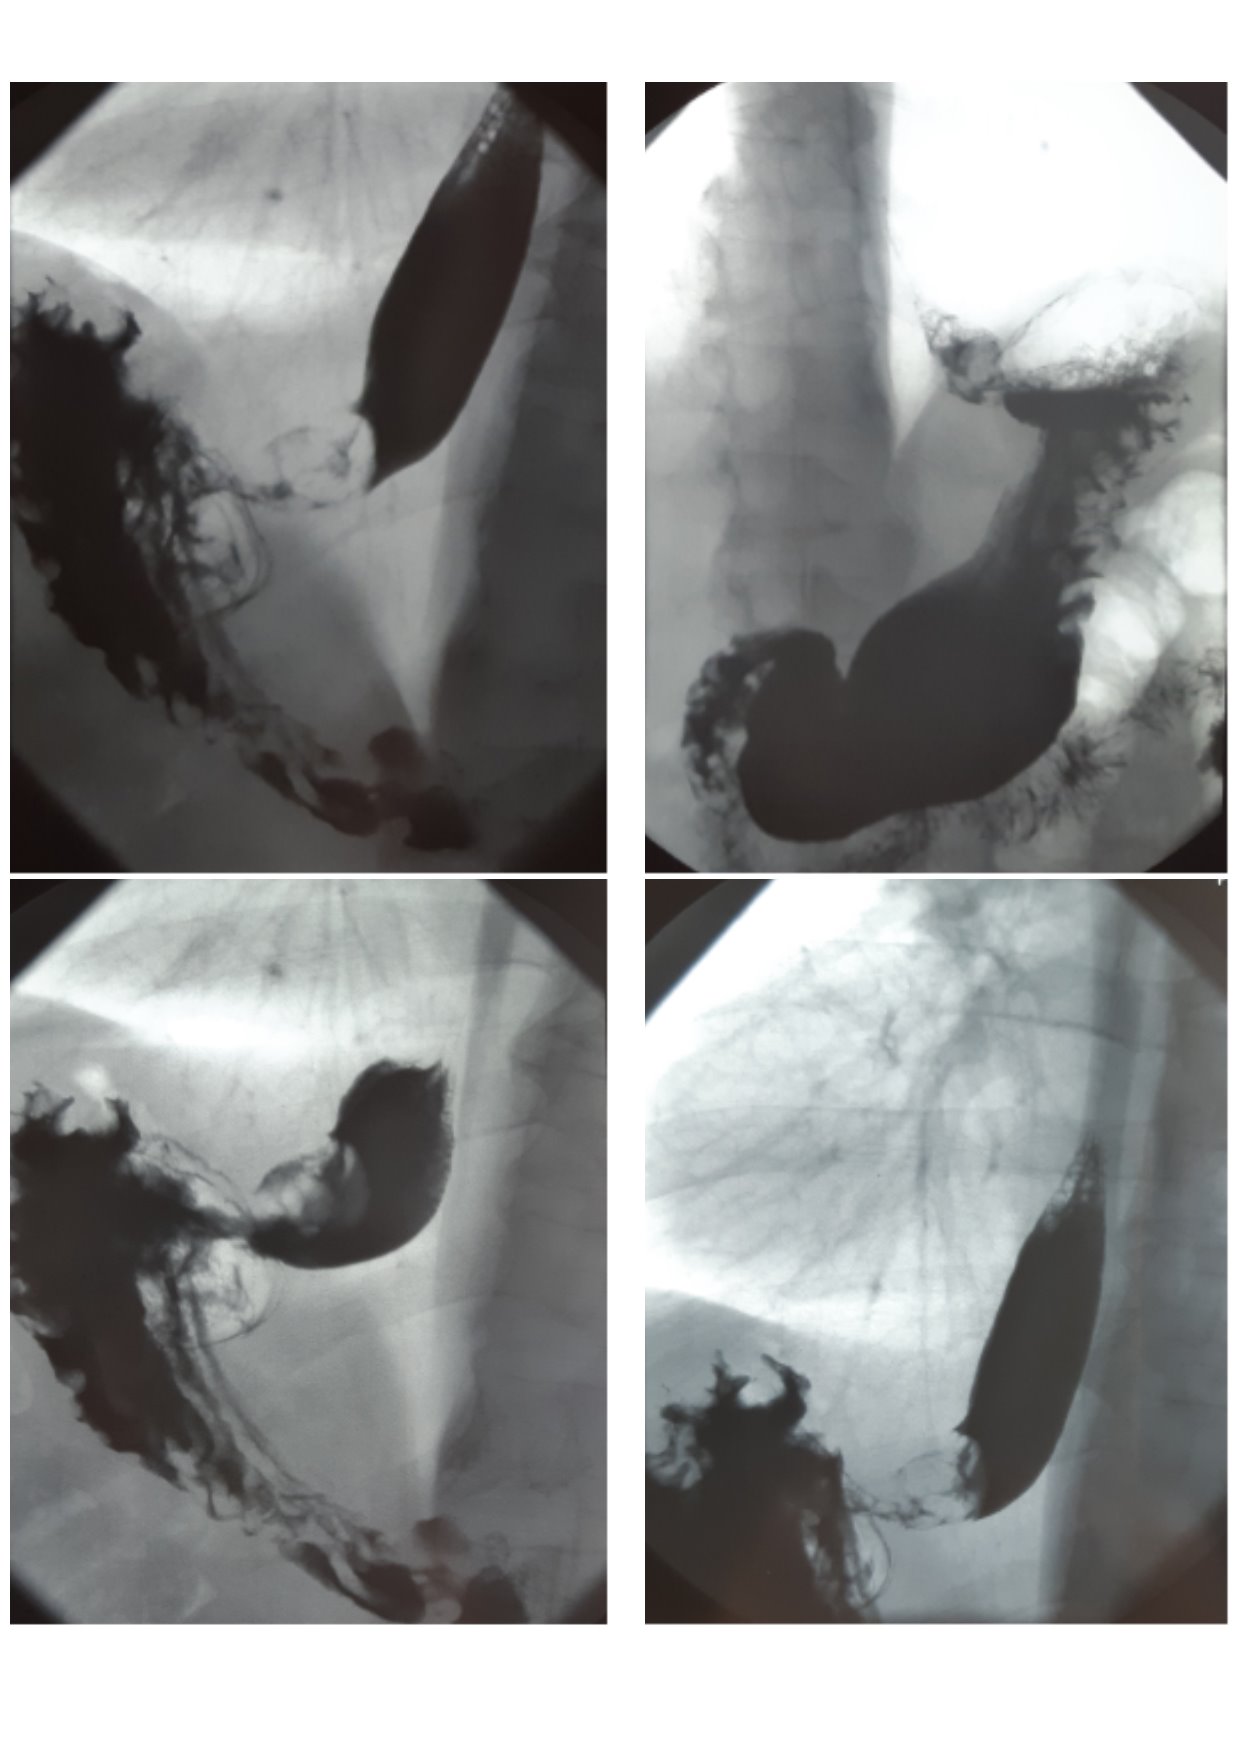

Endoscopic and X-ray examinations (Figure 3) revealed cicatrical stenosis in the zone of gastroanastomose. After per os intake of barium suspension, narrowing of the lumen to 0.4 cm along 0.7 cm length was determined in the region of anastomose in a series of X-ray pictures. Evacuation through the esophagus, transplant, a part of stomach in the abdominal cavity and duodenum was visible.

A course of gullet bougienage under X-ray control was conducted with a positive effect.

Fig. 3. Radiographic contrast examination of the esophagus and stomach in 4 months after surgery